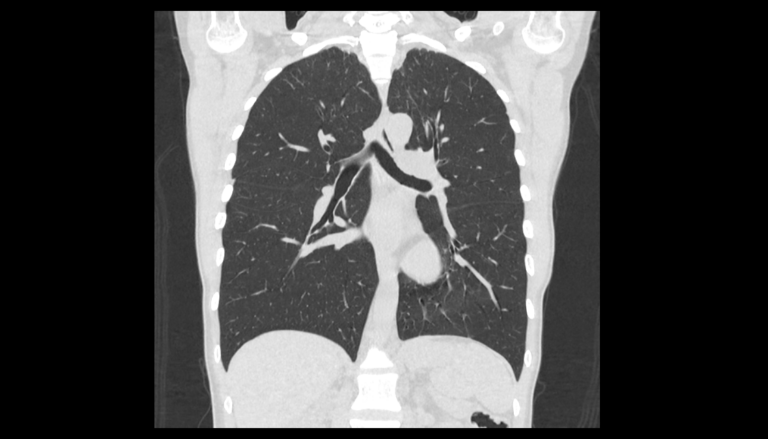

Во время исследования рентгеновская трубка томографа вращается вокруг исследуемой области и производит множество послойных снимков с шагом 0,5-1 мм. Полученные снимки поперечного сечения с помощью компьютерной программы могут быть преобразованы в 3D-изображения исследуемого органа или участка ткани. Это позволяет выявлять практически все заболевания легких на ранних стадиях и назначать своевременное лечение.

В медицинском центре «Доступная медицина» используется современный 128-срезовый компьютерный томограф TOSHIBA AQUILION CXL, на котором проводится сканирование легочной ткани. За счет увеличенного количества детекторов аппарат производит снимки с большой скоростью и минимальной дозой облучения. При этом инновационные цифровые приложения позволяют получить объемные изображения легочной ткани высокой четкости, контрастности и в мельчайших подробностях.